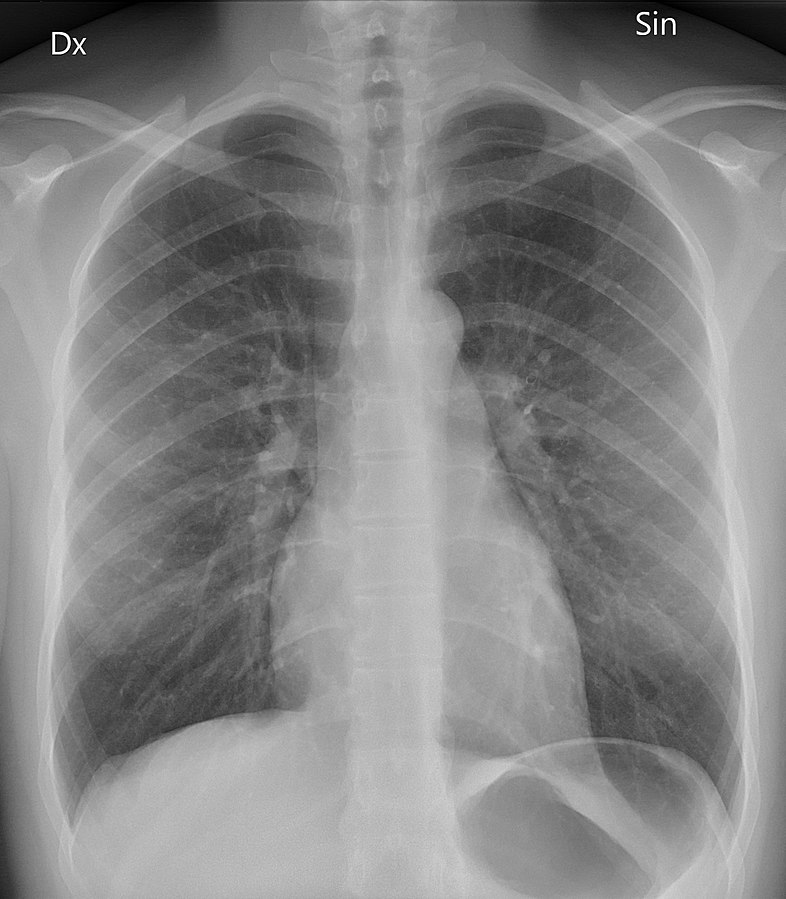

In particular, we focus on classification: a common statistical problem in fields such as medicine. Our motivating example illustrates a classical situation where, given segmented chest X-ray images showing the two lungs and the heart, the task is to detect a morphological anomaly. Specifically, the application concerns cardiomegaly, an anomaly characterized by an abnormally large (relative) heart size. Detecting this condition has been the subject of numerous studies; see, e.g., Lee et al., (2024) and Bougias et al., (2021). However, to our knowledge, most of the methods investigated to date have been pixel-based.

Figure 1 illustrates the image representation used in the proposed image analysis procedure. Panel (a) shows the original X-ray as a collection of pixel intensity values stored as a matrix, while panel (b) displays the masks obtained through image segmentation (Gaggion et al.,, 2024). Panels (c) and (d) present the data we aim to analyze: the contours of the three objects of interest, denoted , and , which can be represented by two coordinate functions, i.e., . Together, these contours form a multivariate planar curve (with ), which constitutes the parsimonious image representation studied in this work.

In this section, we illustrate the practical relevance of our methodology by applying it to a real-world classification problem: detecting cardiomegaly from chest X-ray data. Cardiomegaly refers to an abnormal enlargement of the heart, which manifests on radiographic images as the heart occupying more than half of the thoracic width (see Figure 5). This condition is clinically significant, as it may indicate underlying heart diseases such as heart failure or arrhythmia, which can lead to severe complications including sudden cardiac arrest. Early and accurate detection is therefore essential.

As illustrated in Figure 5, the distinction between healthy and cardiomegalic patients can be subtle: there is high variability in both the shape and the deformations of the anatomical structures, making automated classification challenging.